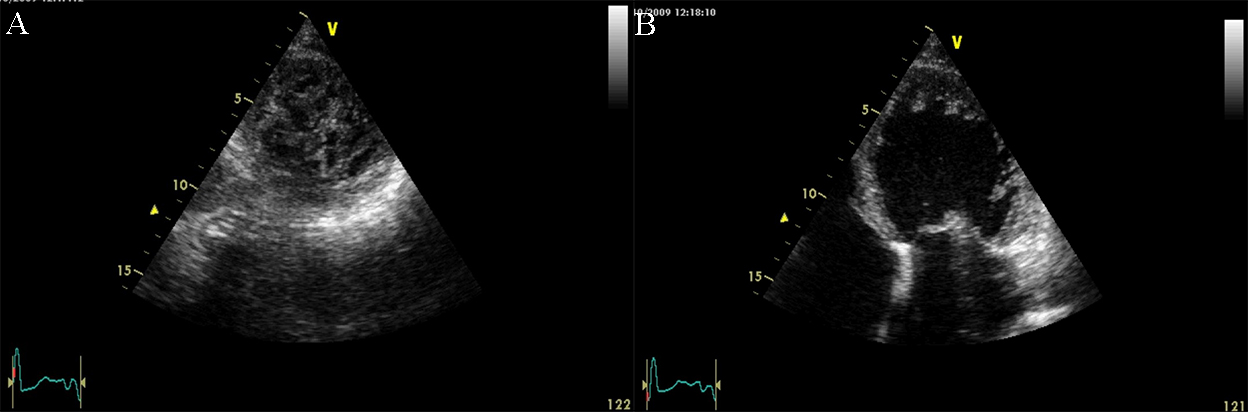

Restrictive cardiomyopathy (RCM) is characterized by non-dilated ventricles, mild or no myocardial hypertrophy with impaired ventricular filling, thus it is defined by abnormal ventricular diastolic function with a normal size LV (see Fig. 8). In the early stages of the disease, the systolic function of the LV is also normal [38].

Fig. 8.The echocardiographic aspect of RCM in an elderly patient presenting with signs and symptoms of heart failure. Apical 4 chamber view showing severe biatrial enlargement, with left atrial thrombus and non-dilated left and right ventricles.